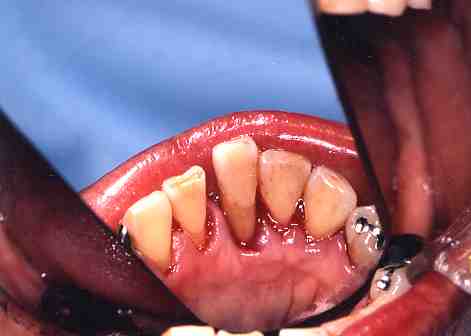

2.歯石をとりました。

歯ぐきが下がって根が

見えています。

支えている骨もなくなって

歯が出てきています。

これが歯周病(歯そうのうろう)

です。

(*このようにならないように3〜6ヶ月

に一度は歯石をとりましょう)